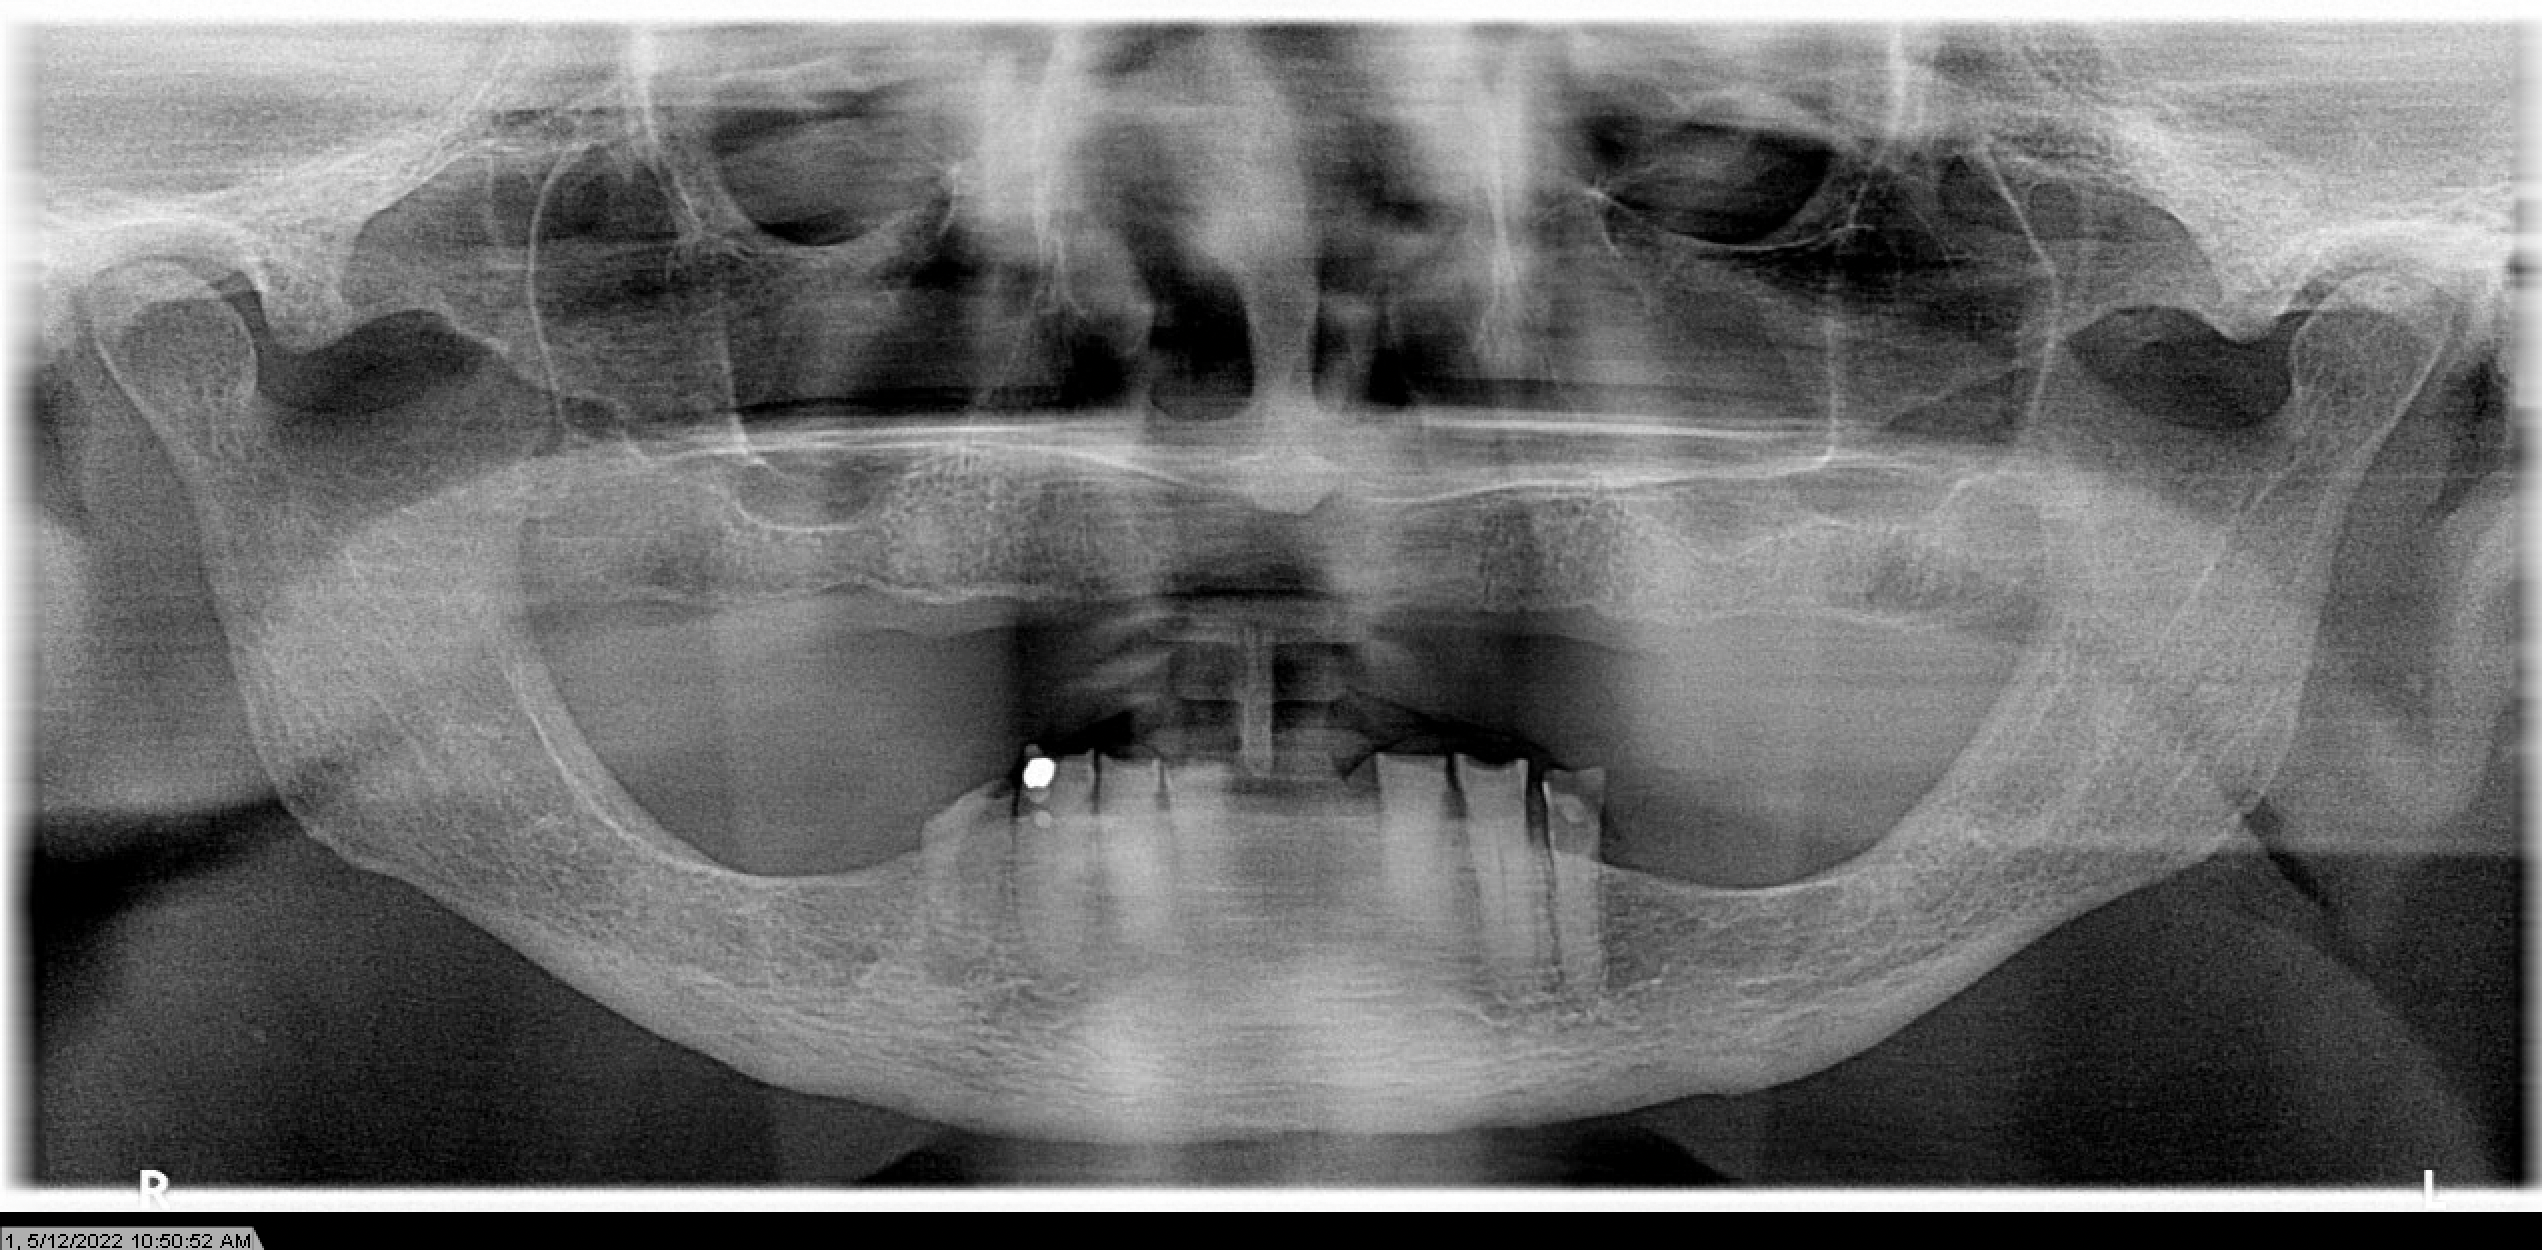

たとえば、上あごには歯が残っていて、下あごの歯がほとんどない場合、上の歯は下方向へ伸びてくることがあります。

このとき、単純に下の歯を補うだけで患者さんが満足できるとは限りません。

上の歯の位置がすでに変わっていれば、下を整えても、見た目やかみ合わせが患者さんの望む状態にならないことがあるからです。

しかも歯の位置異常は、上下方向だけではありません。

横方向にも起こります。

特に骨の支えが減ってくると、上の前歯が前方に出てきたり、外側に張り出したりすることがあります。

こうなると、前歯の見え方が強くなりすぎたり、口元が閉じにくくなったりして、見た目の違和感につながります。

たとえば、前歯が出て見えることを気にされていても、原因は前歯そのものではなく、奥歯を失ったことでかみ合わせが崩れ、前歯が動いてきた結果であることがあります。

あるいは、下の歯がないことより、上の歯が伸びてきたことで、全体の見た目が不自然になっていることもあります。